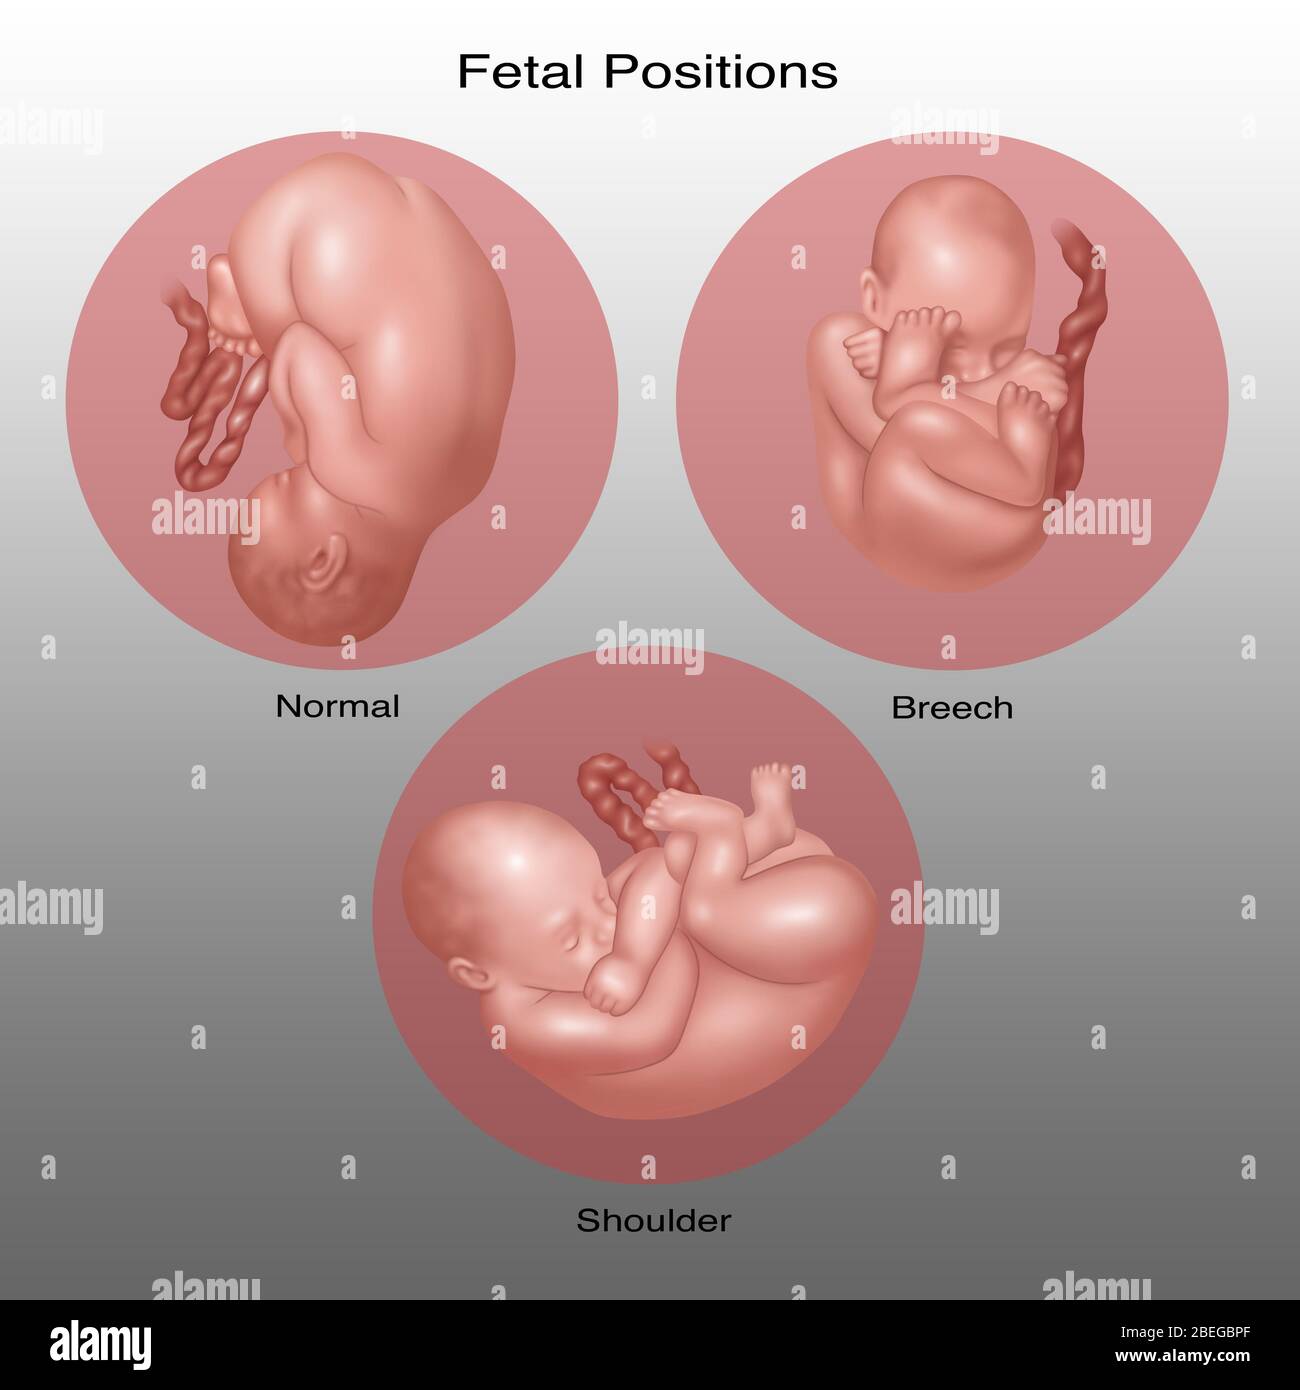

Fetus Positions in Uterus, Illustration Stock Photohttps://www.alamy.com/image-license-details/?v=1https://www.alamy.com/fetus-positions-in-uterus-illustration-image353173031.html

Fetus Positions in Uterus, Illustration Stock Photohttps://www.alamy.com/image-license-details/?v=1https://www.alamy.com/fetus-positions-in-uterus-illustration-image353173031.htmlRF2BEGBPF–Fetus Positions in Uterus, Illustration

Fetus Positions in Uterus, Illustration Stock Photohttps://www.alamy.com/image-license-details/?v=1https://www.alamy.com/fetus-positions-in-uterus-illustration-image353173074.html

Fetus Positions in Uterus, Illustration Stock Photohttps://www.alamy.com/image-license-details/?v=1https://www.alamy.com/fetus-positions-in-uterus-illustration-image353173074.htmlRF2BEGBT2–Fetus Positions in Uterus, Illustration

Fetus Positions in Uterus, Illustration Stock Photohttps://www.alamy.com/image-license-details/?v=1https://www.alamy.com/fetus-positions-in-uterus-illustration-image353173049.html

Fetus Positions in Uterus, Illustration Stock Photohttps://www.alamy.com/image-license-details/?v=1https://www.alamy.com/fetus-positions-in-uterus-illustration-image353173049.htmlRF2BEGBR5–Fetus Positions in Uterus, Illustration

Fetus in Shoulder Position, Illustration Stock Photohttps://www.alamy.com/image-license-details/?v=1https://www.alamy.com/fetus-in-shoulder-position-illustration-image353173032.html

Fetus in Shoulder Position, Illustration Stock Photohttps://www.alamy.com/image-license-details/?v=1https://www.alamy.com/fetus-in-shoulder-position-illustration-image353173032.htmlRF2BEGBPG–Fetus in Shoulder Position, Illustration

Fetus Positions in Uterus, Illustration Stock Photohttps://www.alamy.com/image-license-details/?v=1https://www.alamy.com/fetus-positions-in-uterus-illustration-image353173070.html

Fetus Positions in Uterus, Illustration Stock Photohttps://www.alamy.com/image-license-details/?v=1https://www.alamy.com/fetus-positions-in-uterus-illustration-image353173070.htmlRF2BEGBRX–Fetus Positions in Uterus, Illustration

Fetus Positions in Uterus, Illustration Stock Photohttps://www.alamy.com/image-license-details/?v=1https://www.alamy.com/fetus-positions-in-uterus-illustration-image353173044.html

Fetus Positions in Uterus, Illustration Stock Photohttps://www.alamy.com/image-license-details/?v=1https://www.alamy.com/fetus-positions-in-uterus-illustration-image353173044.htmlRF2BEGBR0–Fetus Positions in Uterus, Illustration